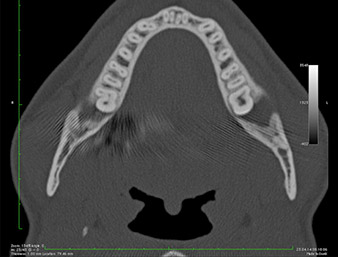

Der Wurzelrest regio 38 zeigte bereits in der Panoramaschichtaufnahme eine enge Lagebeziehung zum Nervus alveolaris inferior. (Abb. 1)

In der 3D-Aufnahme (digitales Volumentomogramm) war ersichtlich, dass sich der Wurzelrest weit disto-kaudal im Übergang vom horizontalen zum aufsteigenden Anteil des Unterkiefers befand (Abb. 2).